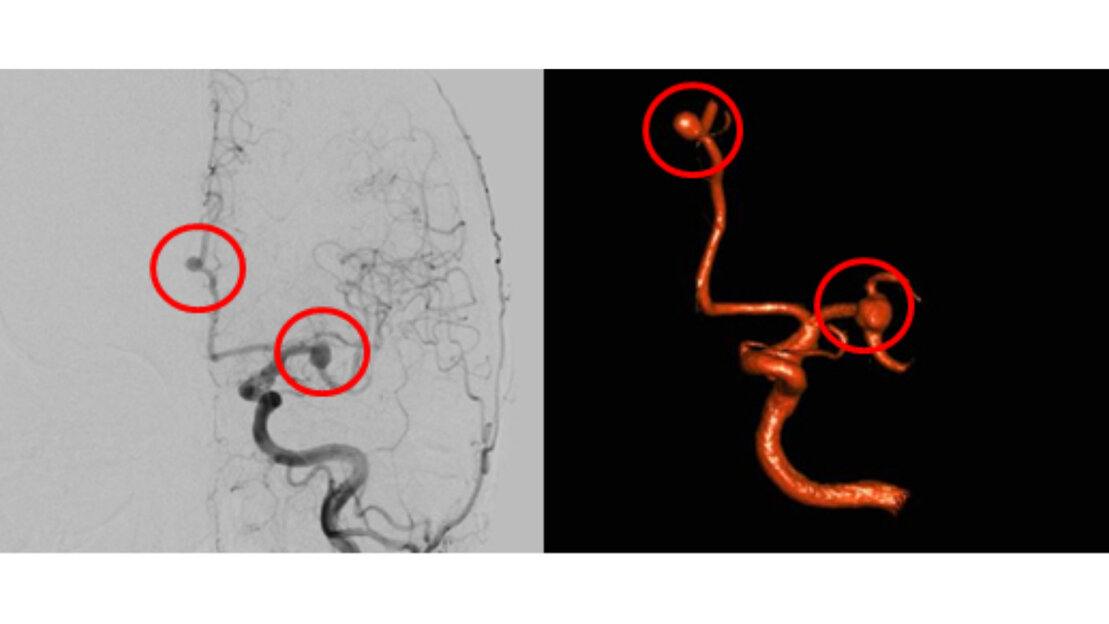

Zur Behandlung eines Aneurysma stehen zwei unterschiedliche Methoden zur Verfügung. Zum einen der interventionelle Verschluss mittels Metallspiralen (engl. Coils – deshalb auch als Coiling bezeichnet), die über einen von der Leiste vorgeschobenen Katheter in das Aneurysma eingebracht werden. Diese Therapieoption wird von einem Neuroradiologen durchgeführt. Zum anderen der Verschluss mit einem Clip (Clipping), der während einer neurochirurgischen Operation auf den Hals des Aneurysma gesetzt wird. Heutzutage ist hierzu in den meisten Fällen nur eine kleine Schädeleröffnung (Minikraniotomie) erforderlich, um den Clip sicher zu platzieren. Wichtig ist die Überprüfung der Hirndurchblutung, die durch den Clip nicht beeinträchtigt sein sollte. Neben der Erfahrung unserer vaskulären Neurochirurgen stehen zur Sicherung eines optimalen Behandlungserfolges auch modernste Techniken zur Verfügung. Zu unserem Behandlungsstandard gehören mikrochirurgische Verfahren, die von neusten endoskopischen Techniken unterstützt werden. Die intraoperative Darstellung der Hirngefäße mit Fluoreszenzfarbstoffen (ICG-Videoangiographie und ICG-Endoskopie) garantiert zusammen mit intraoperativen Ultraschalluntersuchungen und funktionellem Neuromonitoring ein bestmögliches postoperatives Resultat.

Hierbei handelt es sich um Gefäßaussackungen der hirnversorgenden Gefäße, meist an der Schädelbasis. Kommt es zum Platzen (Ruptur) eines Aneurysma resultiert hieraus eine Hirnblutung, in der Regel eine Subarachnoidalblutung (SAB). Die Subarachnoidalblutung ist trotz wesentlicher Verbesserungen in der medizinischen Versorgung immer noch mit einer hohen Sterblichkeit oder im Falle des Überlebens oftmals mit bleibenden Schäden verbunden. Bei erfolgter Ruptur ist eine unmittelbare Therapie zu empfehlen. Aber auch bei zufälliger Entdeckung eines Aneurysmas ohne Blutung ist eine frühzeitige Beratung in einem Fachzentrum ratsam.